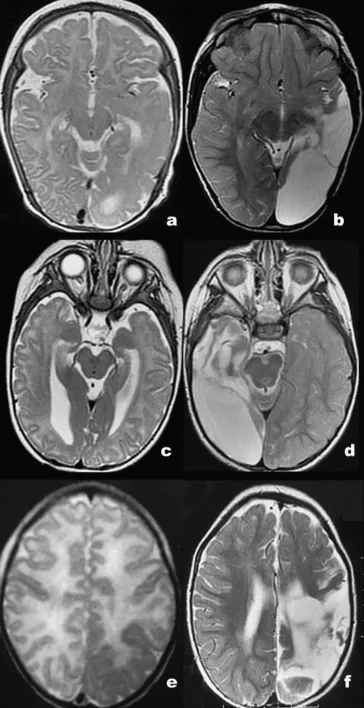

图1:病例1(a、b)、病例2(c、d)与病例3(e、f)术前(a、c、e)及术后(b、d、f)轴位T2加权成像显示患侧枕叶及颞顶叶容积缩小,伴弥漫性皮质不规则增厚。病例1和病例3以多小脑回为主,病例2为巨脑回;病变皮质与未髓化的皮质下白质相比呈轻度低信号。术后图像可见颞-顶-枕区脑脊液充填的手术残腔。